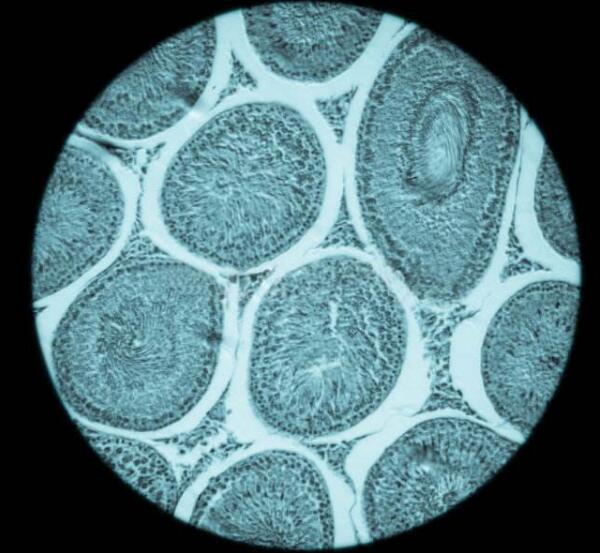

正常情况下,随着卵泡的生长发育,会逐渐变大并形成半月牙似的卵泡腔,腔内充满卵泡液,由卵泡细胞的分泌物和卵泡膜血管渗出液组成,里面还含有营养液。而卵泡的分泌物内有类固醇激素和多种生物活性物质,对卵泡的发育成熟起着至关重要的作用。随着卵泡液的逐渐增多,卵泡腔也会增大,卵母细胞会居于卵泡的一侧,并与周围的颗粒细胞一起突向卵泡腔,形成卵丘。在卵泡腔周边的细胞就会构成卵泡壁,随着卵泡的发育,卵泡膜会分化为内、外两层。

而在B超监测下可以看到卵泡发育正常,但在取卵的时候却发生空卵现象,主要是与这些因素有关:一是卵子早期即发生闭锁,但卵泡受激素刺激仍继续生长;二是卵巢反应不良、卵母细胞发育障碍和卵巢对HCG反应不良导致;三是卵泡液内分泌异常使卵泡中缺少HCG,或促排卵时HCG作用时间不长就取卵,不足以使卵丘复合物从卵壁脱落;四是可能与促排卵药物的使用不当相关。